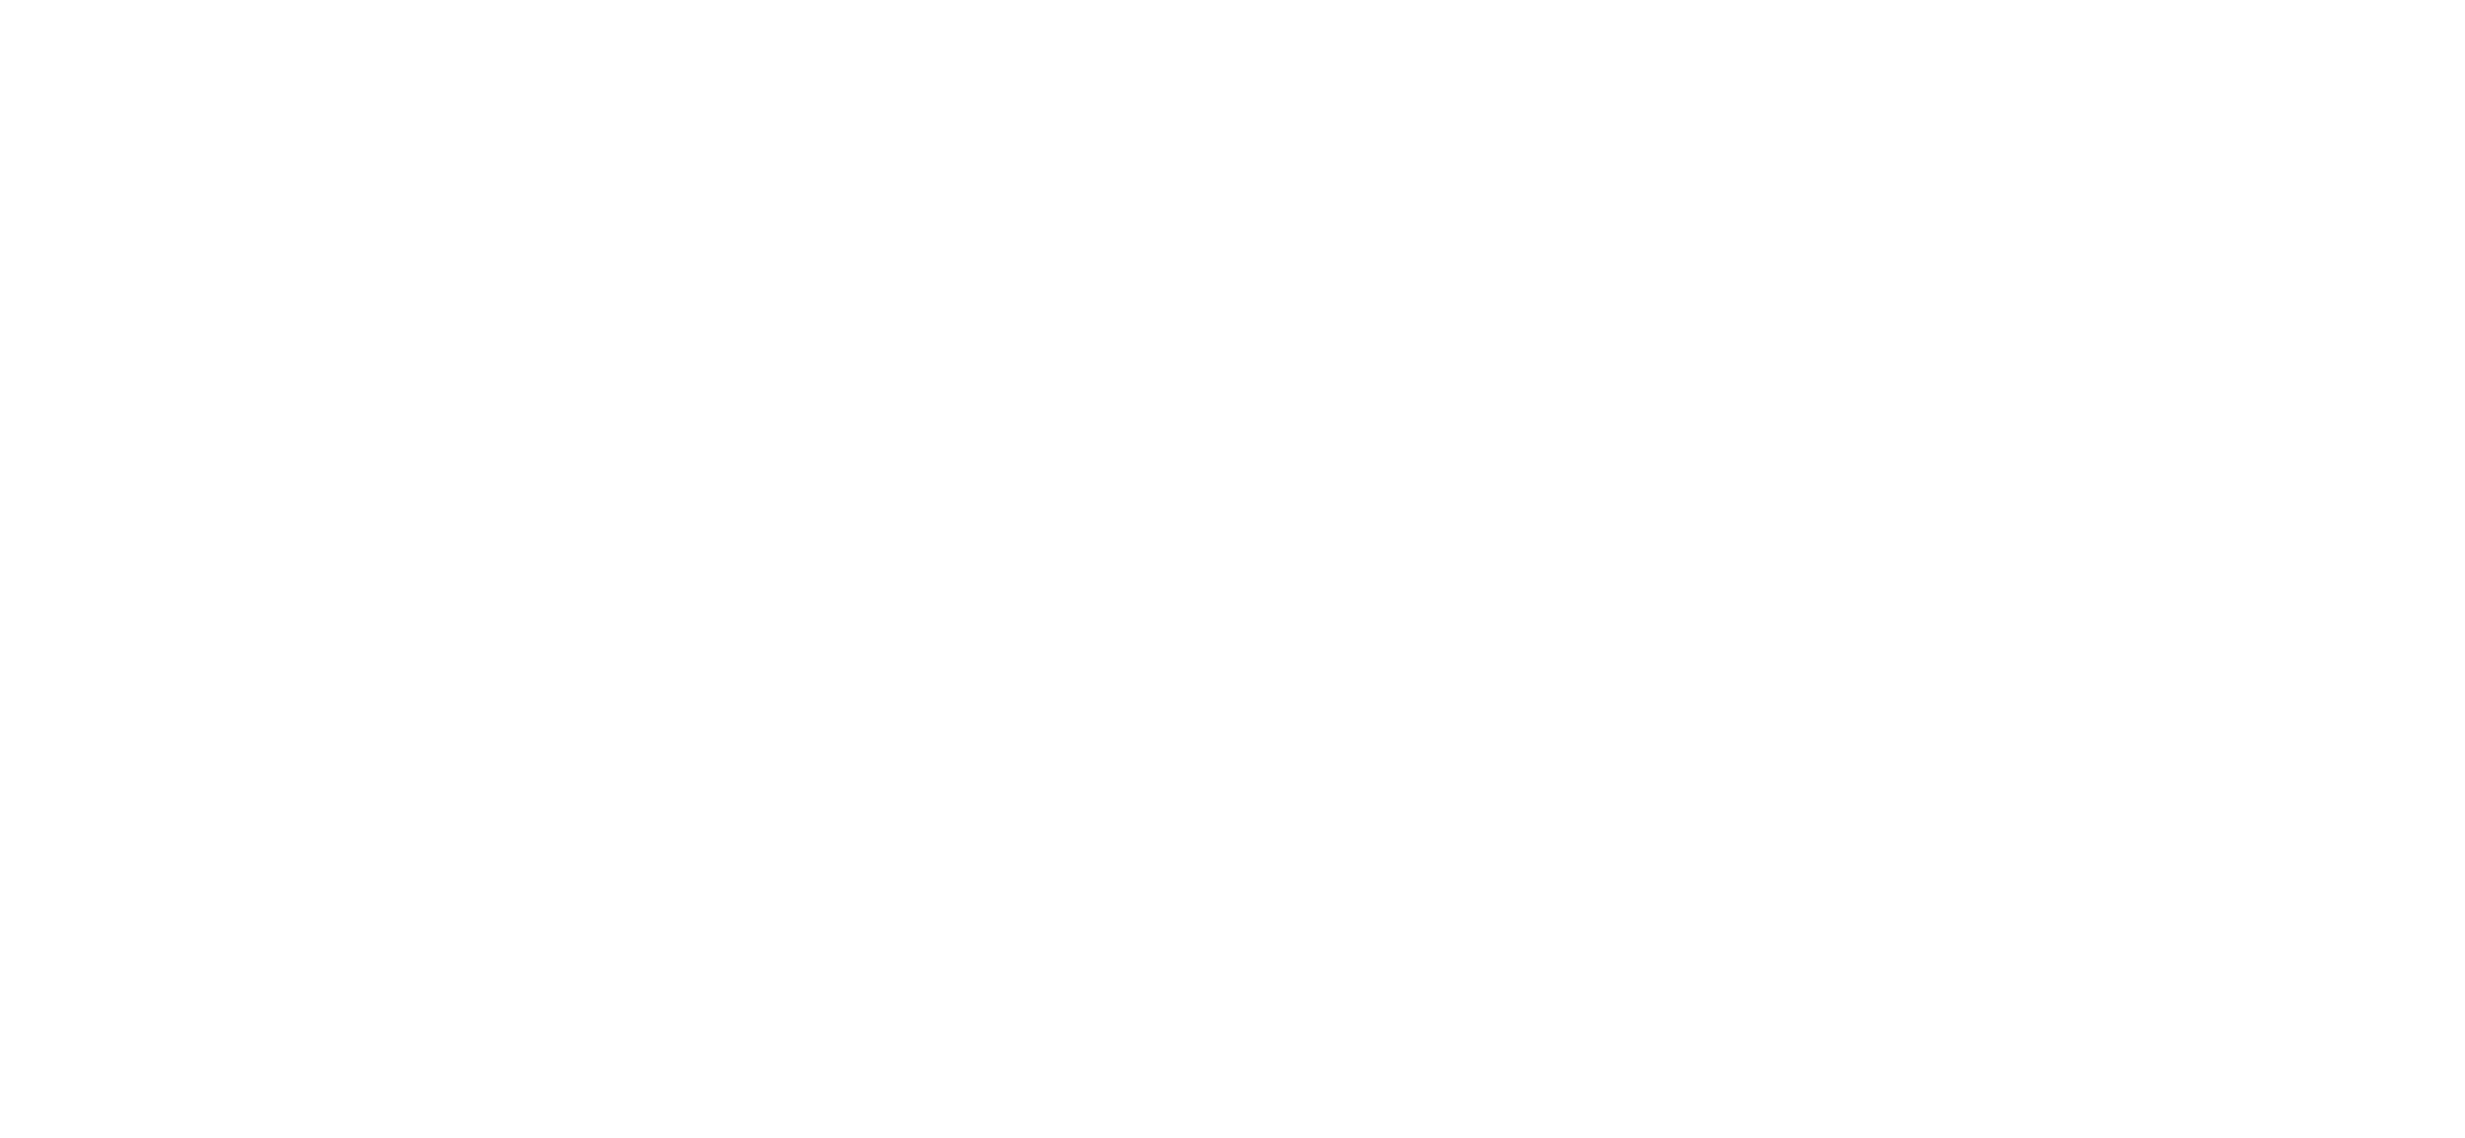

Here is a glimpse of Baby Hannah coming into the world, baby #8 for this family!!! Their oldest daughter asked to come along to witness the birth which I thought was so cool. And mommy used hypnobabies to get through the labor and she did an amazing job!